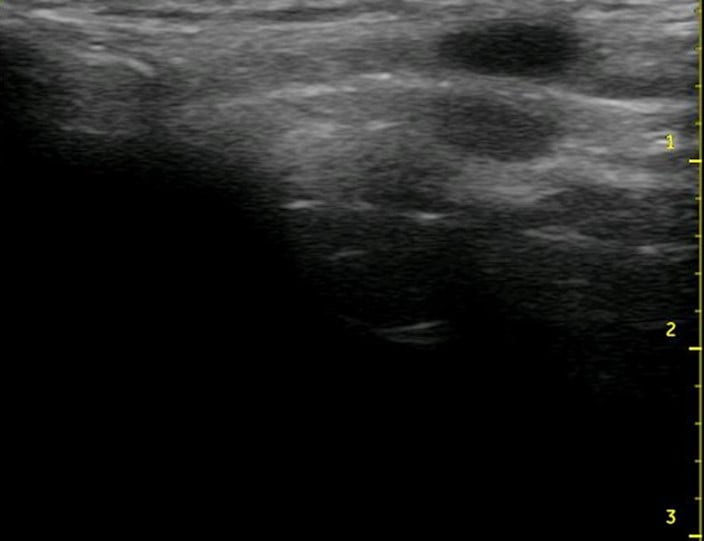

In contrast to native cartilage, which is hypoechoic with posterior shadowing, the plastic model of the thyroid cartilage and cricoid cartilage appear hyperechoic with more dense posterior shadowing (below). This model performs well as an ultrasound-guided cric training model. It has realistic anatomy. It models a patient with difficult to palpate anatomy, which are patient who may be difficult to intubate and may be more likely to need cricothyrotomy in the first place. The overlying skin and pre-tracheal ballistic gel can be easily and quickly replaced for the next operator in a training setting. The model allows for performing all the steps of cricothyrotomy including passing the bougie and ETT. The model is durable and re-usable.

Figure 6. Midsagittal ultrasound of the anterior neck of a live person

Figure 7. Midsagittal ultrasound of the anterior neck of the model